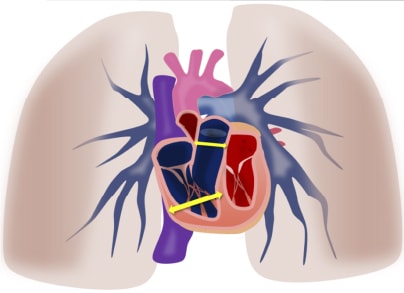

肺高血圧の特徴的な所見は

右心負荷や肺動脈拡張です